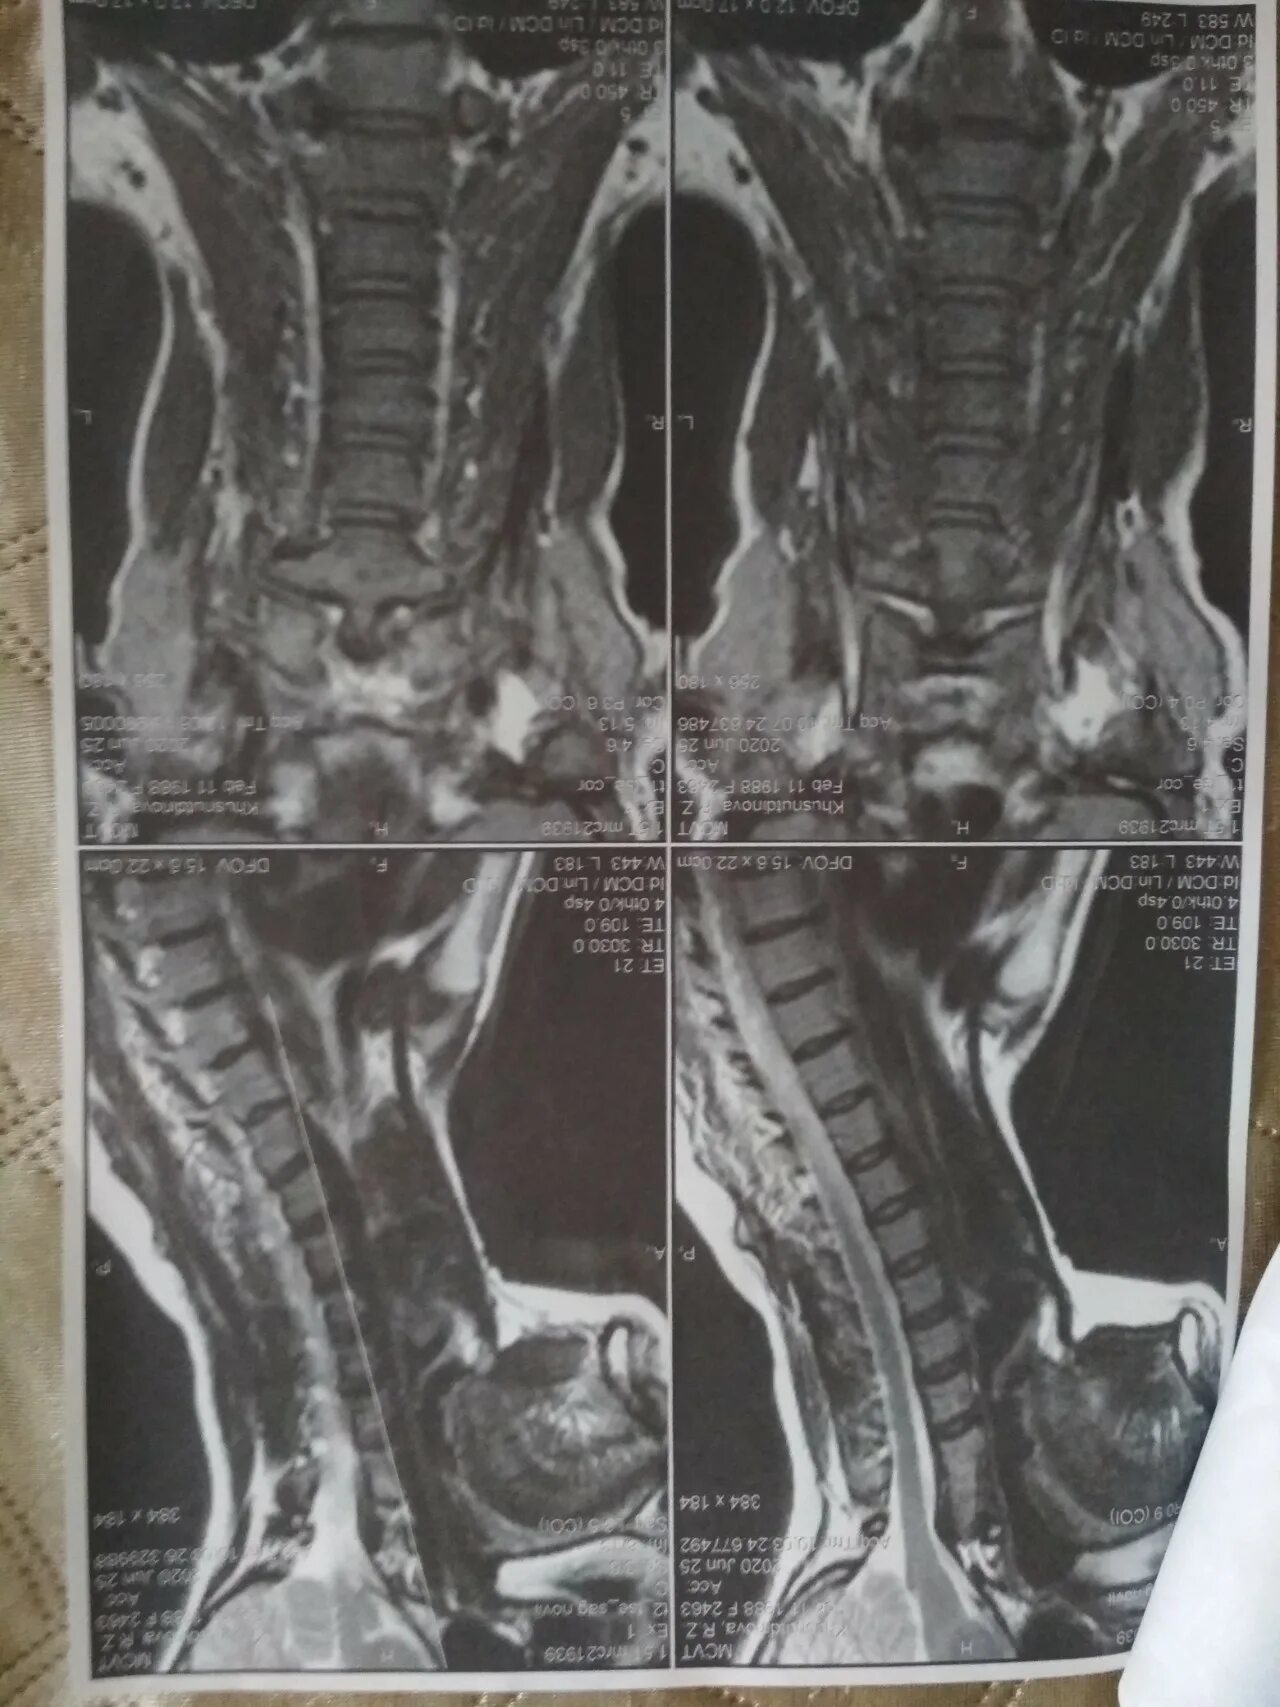

Сколько по времени делается мрт шейного отдела